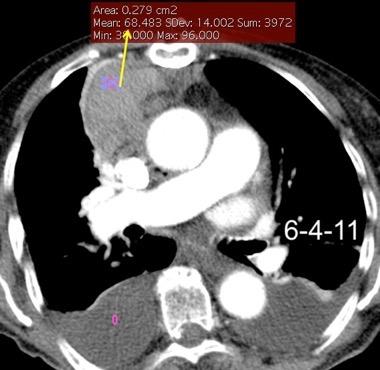

32 años .Preeclampsia a los 19. Hipertensión no controlada. Masa paravertebral sólida que se realza intensamente con afectación ósea.

Yue Y t al. Asymptomatic left posterior mediastinal functional Paraganglioma. A case report. Medicine . 2019